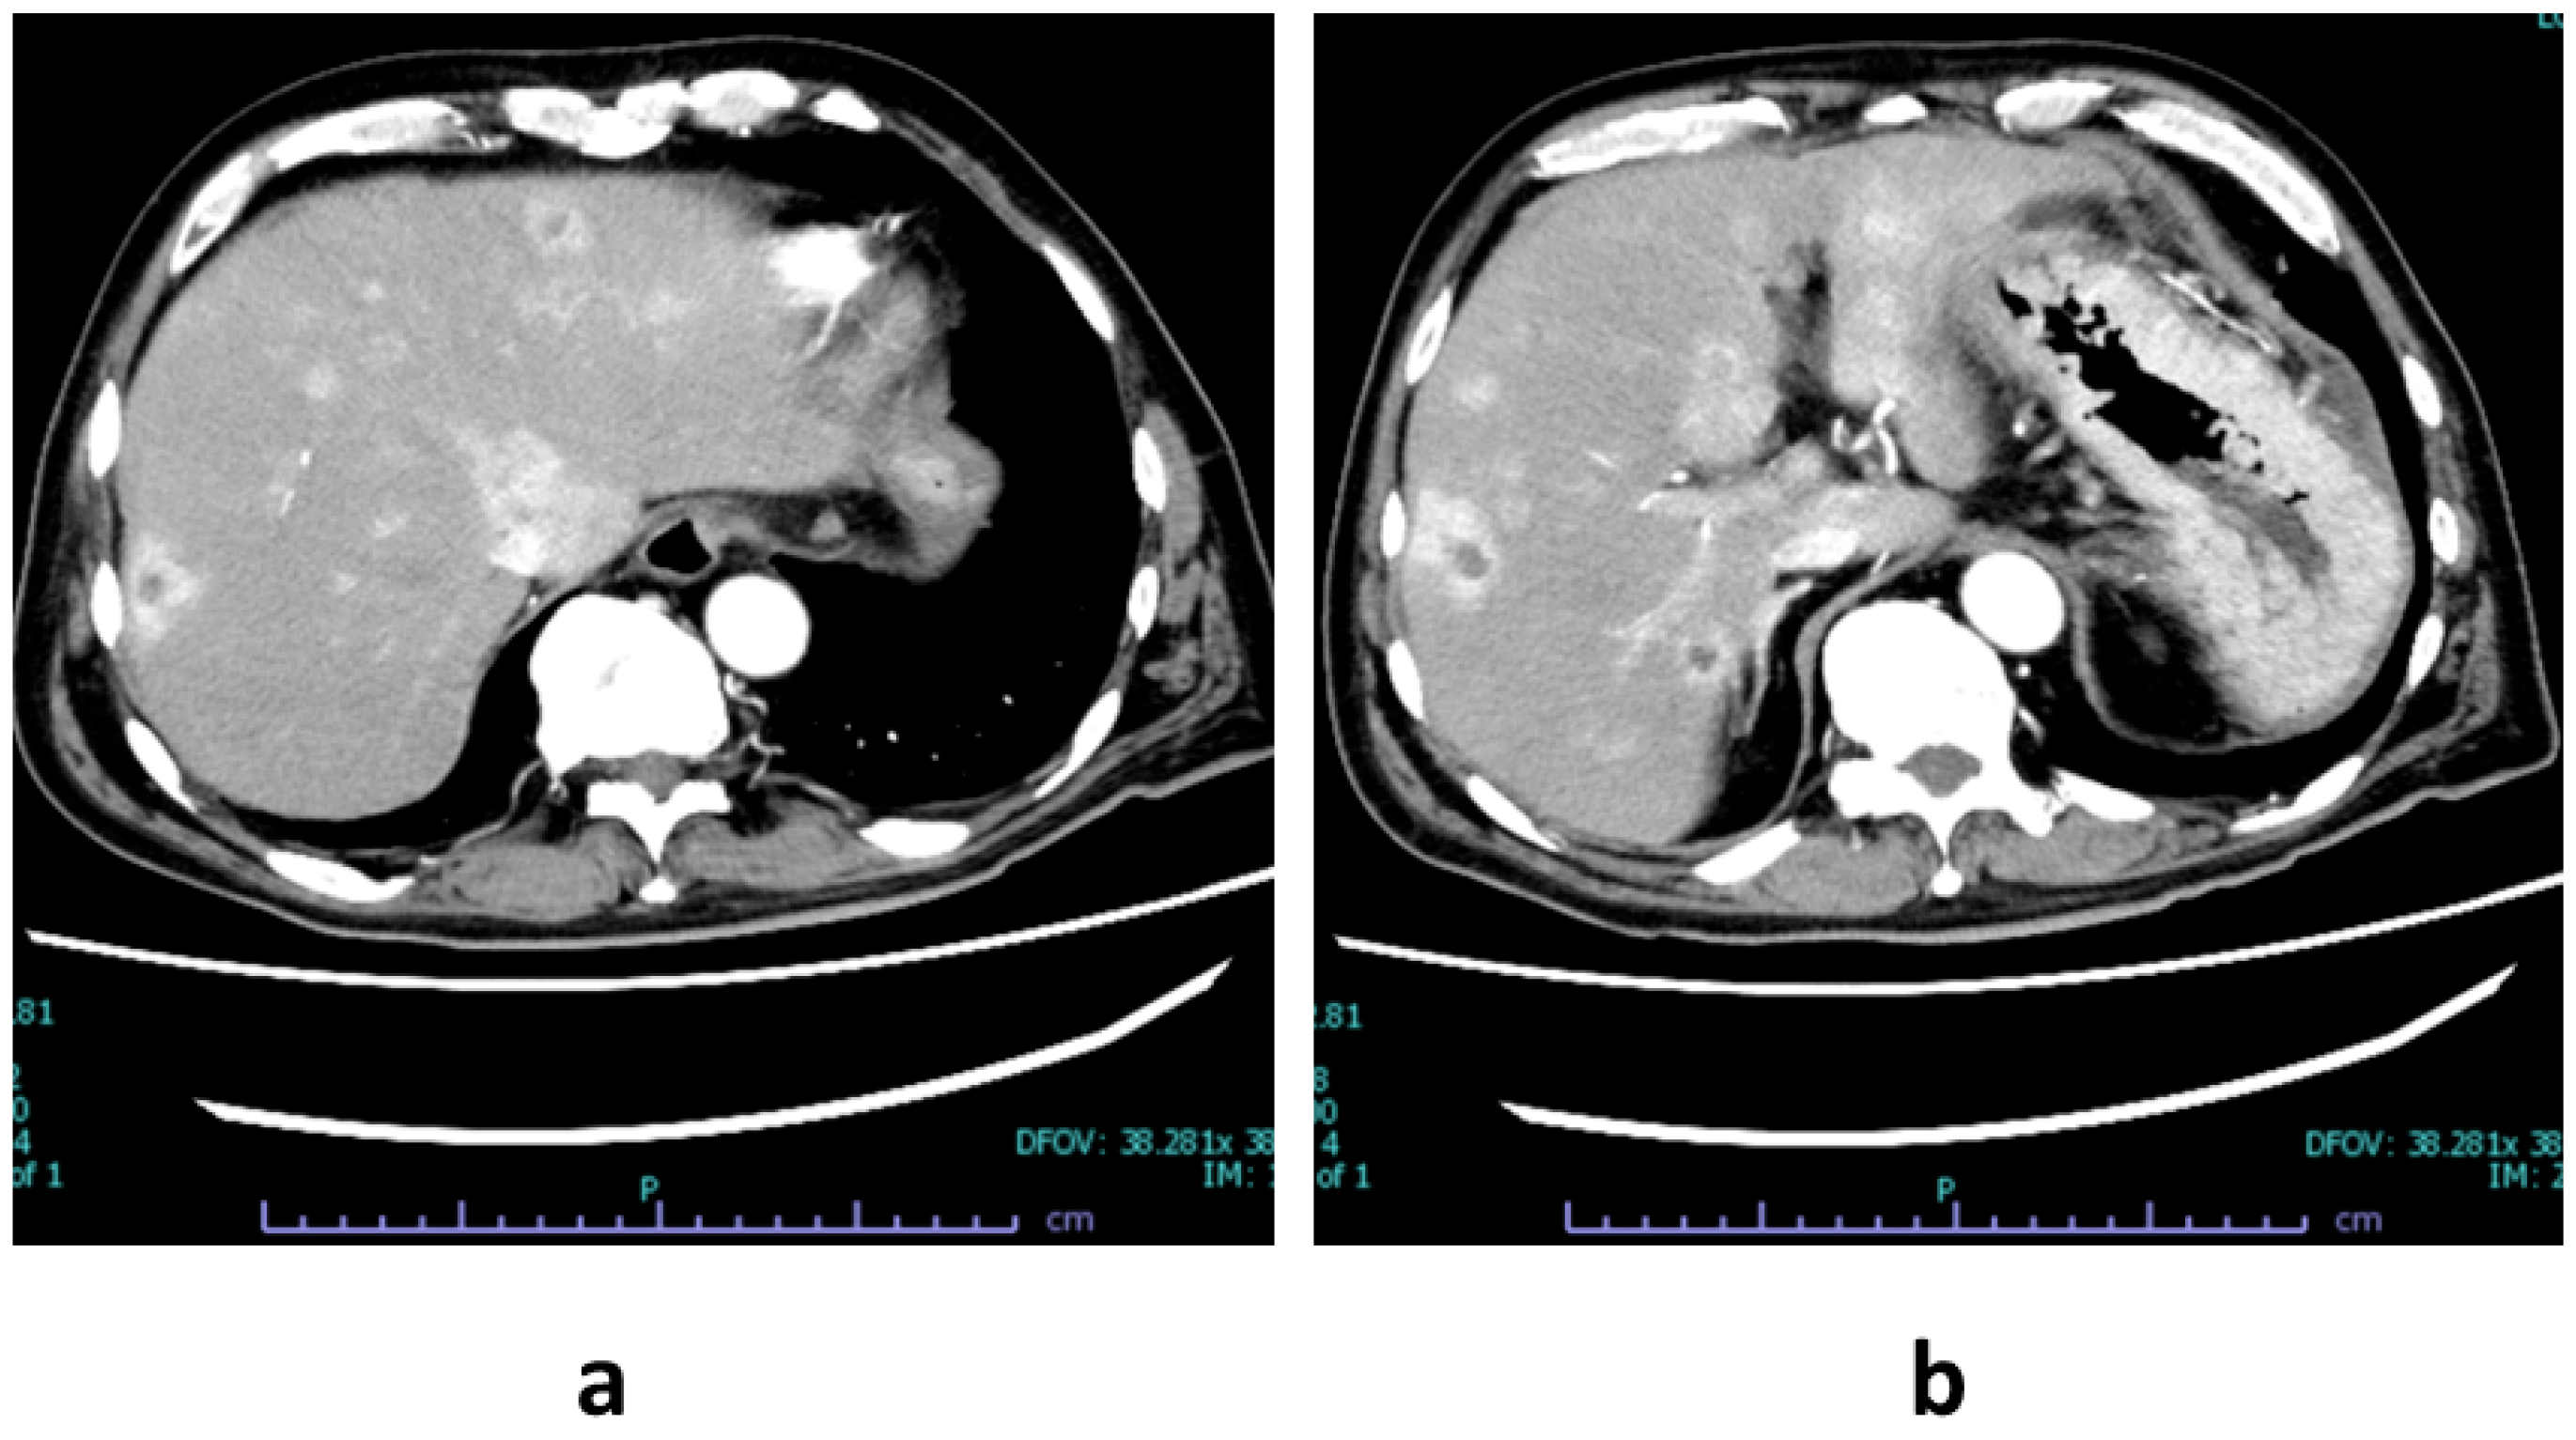

2. Case Presentation